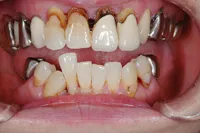

重度の歯槽膿漏のケース

■治療前

■治療後

治療のポイント

上下に入れ歯を入れていましたが、ここ数年しっかりと噛む事がなかった患者様です。何でもおいしく食事ができるようになりたいと希望され、来院されました。

治療法としては、最小限のインプラントの本数で対応ができるように、オールオンフォーを意識した治療法で対応させて頂きました。

| 主訴 | 噛めない |

|---|---|

| 治療方法 | 上顎8本、下顎6本のインプラントを埋入し固定性の入れ歯で治療した |

| 治療期間 | 約1年 |

| 通院回数等 | 20回 |

| 費用 | 上顎4,130,000円 下顎3,630,000円(税込) |

| リスク・副作用 | 治療後に一時的に腫れることがある |